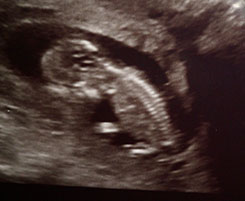

Once i see little squidge on the monitor suddenly the urge to pee goes right out of my head and my eyes are fixed on the screen. My little baby, There. Peacefully sleeping.

Suddenly it turned, Faces right towards us for a few seconds. I can see its little face and then rolls over and puts its back towards us. Definitely doesn't get that from me =P

The woman rolls the wand around my tummy where baby is and She/He turns over. Hands go straight into the air. Feet kicking all over the place and starts to do somersaults then sits up. The most amazing experience iv ever had!

It was seriously the bestest feeling in the world and now its suddenly become so real. I can now put a picture to the little heartbeat i hear through the doppler.

Baby Squidge Due 9th August